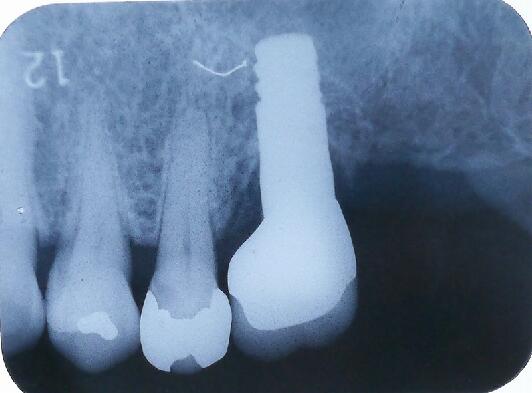

その部位の拡大エックス線像です

上顎には他の場所と違い上顎洞という頭を軽くするための空洞があり骨が2〜4ミリ程度しかなく、インプラントは大変困難です。

前方から見たエックス線像

オペ当日のエックス線写真です

4ヵ月後のエックス線写真です すでに骨が出来ております